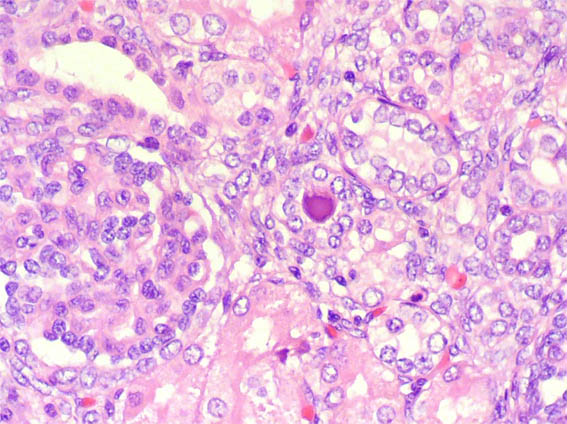

En ambos riñones fetales se observa lo mostrado en las siguientes imágenes.

Figura 2.

H&E, X400.